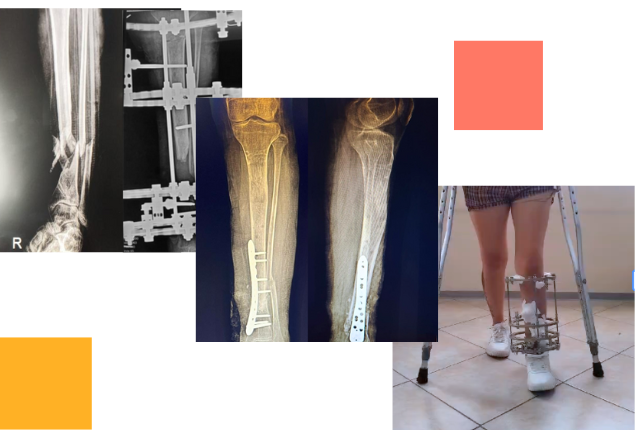

Tras un accidente de tránsito, Yessenia presentó una fractura expuesta con un defecto óseo de 10 cm en su pierna. Había recibido tratamientos previos sin éxito y su movilidad estaba en riesgo.

Con la técnica de osteogénesis por distracción y el uso de un tutor circular Ilizarov, se inició un proceso de regeneración ósea progresiva, acompañado de un seguimiento cercano.

Hoy Yessenia evoluciona favorablemente, conserva movilidad en su rodilla y tobillo, y está recuperando la independencia que pensaba perdida.